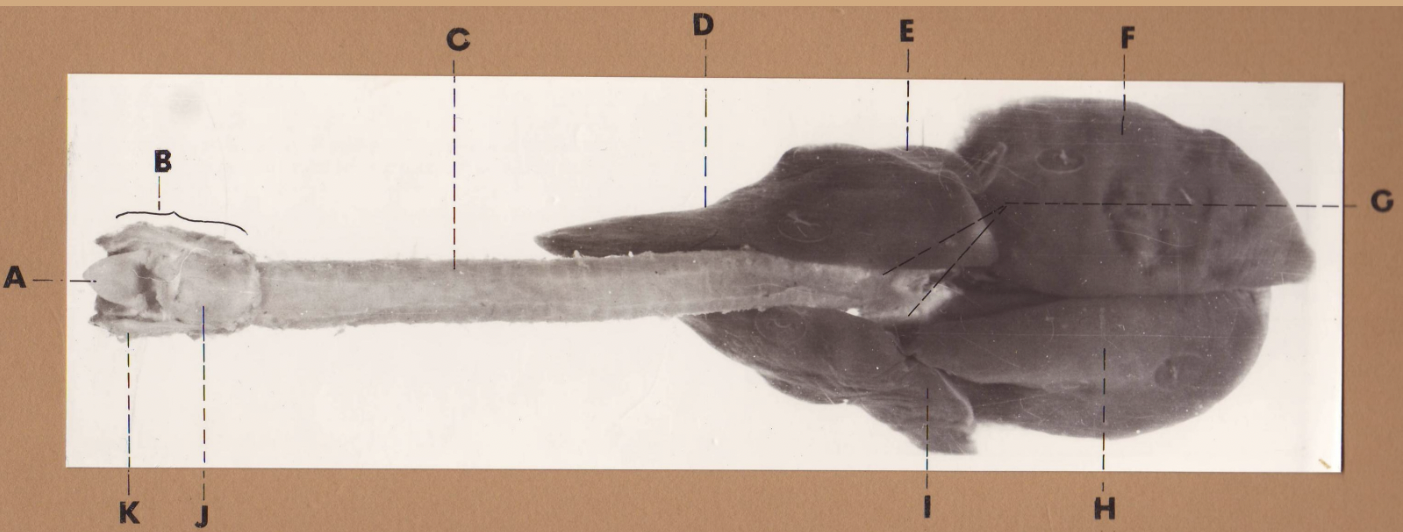

A

(cat larynx/trachea/lungs, dorsal)

epiglottis

B

(cat larynx/trachea/lungs, dorsal)

larynx

C

(cat larynx/trachea/lungs, dorsal)

trachea

D

(cat larynx/trachea/lungs, dorsal)

R cranial lobe

E

(cat larynx/trachea/lungs, dorsal)

middle lobe

F

(cat larynx/trachea/lungs, dorsal)

R caudal lobe

G

(cat larynx/trachea/lungs, dorsal)

primary bronchi

H

(cat larynx/trachea/lungs, dorsal)

L caudal lobe

I

(cat larynx/trachea/lungs, dorsal)

L cranial lobe

J

(cat larynx/trachea/lungs, dorsal)

cricoarytenoideus dorsalis m

K

(cat larynx/trachea/lungs, dorsal)

thyroid

A

(cat larynx/trachea/lungs, dorsal)

epiglottis

B

(cat larynx/trachea/lungs, dorsal)

larynx

C

(cat larynx/trachea/lungs, dorsal)

trachea

D

(cat larynx/trachea/lungs, dorsal)

R cranial lobe

E

(cat larynx/trachea/lungs, dorsal)

middle lobe

F

(cat larynx/trachea/lungs, dorsal)

R caudal lobe

G

(cat larynx/trachea/lungs, dorsal)

primary bronchi

H

(cat larynx/trachea/lungs, dorsal)

L caudal lobe

I

(cat larynx/trachea/lungs, dorsal)

L cranial lobe

J

(cat larynx/trachea/lungs, dorsal)

cricoarytenoideus dorsalis m

K

(cat larynx/trachea/lungs, dorsal)

thyroid